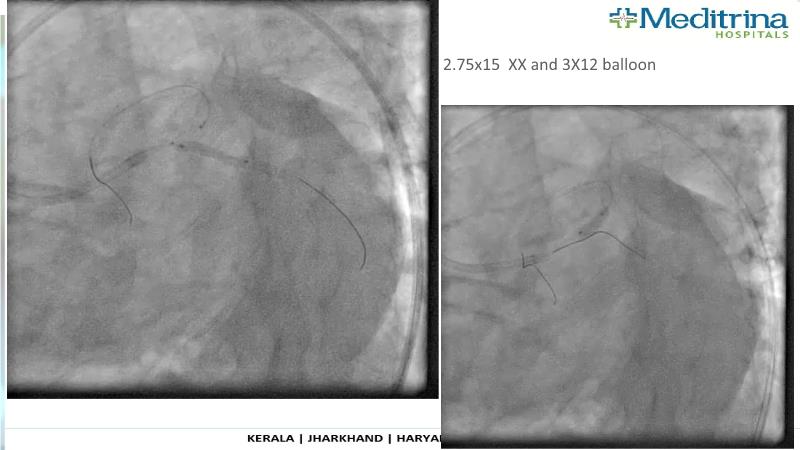

- To define the use of OCT in PCI of complex coronary lesions